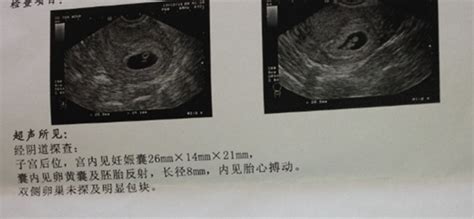

怀孕八个月B超结果如下:双顶径80mm.胎心率132次/分,股骨长59mm,羊水深约61mm,内透声好。胎盘附于子宫前壁,厚约28mm,绒毛板轻度起伏。这样正常吗,知不知道有几斤?谢谢

2000克左右!

31周左右,一切正常!